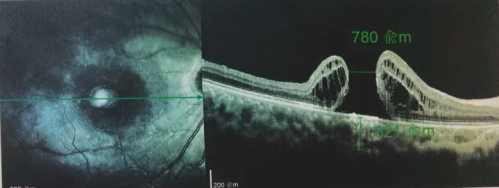

由于自身患有頸椎病,每次術(shù)后長期的趴睡都讓他痛苦不堪。為了尋求更好的治療,吳爺爺來到廈門大學(xué)附屬廈門眼科中心,找到了眼外傷及眼底病2科的李海波博士后。此時,吳爺爺右眼的黃斑裂孔已經(jīng)持續(xù)擴(kuò)大到780μm,演變?yōu)殡y治性的大裂孔。

最讓吳爺爺難以置信的是:術(shù)后只需保持平躺24小時!第二天復(fù)查時,眼底鏡及OCT檢查清晰顯示——那個折磨了他大半年的大裂孔,竟然閉合了!且吳爺爺?shù)挠已垡暳τ辛嗣黠@的改善,術(shù)后3天已經(jīng)可以看到 0.15。